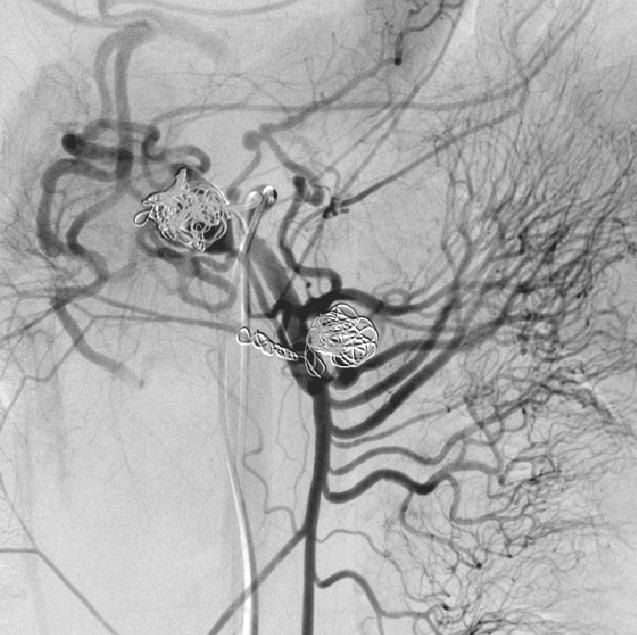

胰十二指肠上、下动脉瘤(sandwich 技术+瘤囊填塞技术)

肠系膜上动脉造影显示胰十二指肠上动脉后弓及前弓各有动脉瘤 |

选择性第一空肠动脉造影显示胰十二指肠下动脉起自第一空肠动脉,其起始部见假性动脉瘤 |

微导管经瘤腔释放微弹簧圈阻塞动脉瘤远端胰十二指肠下动脉前弓,避免侧支动脉充盈动脉瘤 |

阻断动脉瘤远端后同时进行动脉瘤内填塞 |

肠系膜上动脉胰十二指肠下动脉另一分支造影显示其起始部动脉瘤 |

动脉瘤囊内微弹簧栓子填塞 |

填塞后 |

术后动脉造影 |